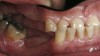

Figure 1  Intraoral anterior view of the patient presenting a severely worn maxillary dentition and loss of OVD.

Figure 1

Initial examination revealed a partial edentulous patient with extensive wear of the maxillary anterior teeth and moderate wear in the mandibular teeth (Figure 1, Figure 2, Figure 3, Figure 4, Figure 5, Figure 6 and Figure 7). The patient’s maxillary and mandibular RPDs also showed excessive wear and multiple signs of fractures (Figure 2 and Figure 3). The patient had been wearing a mandibular nightguard for 8 years.